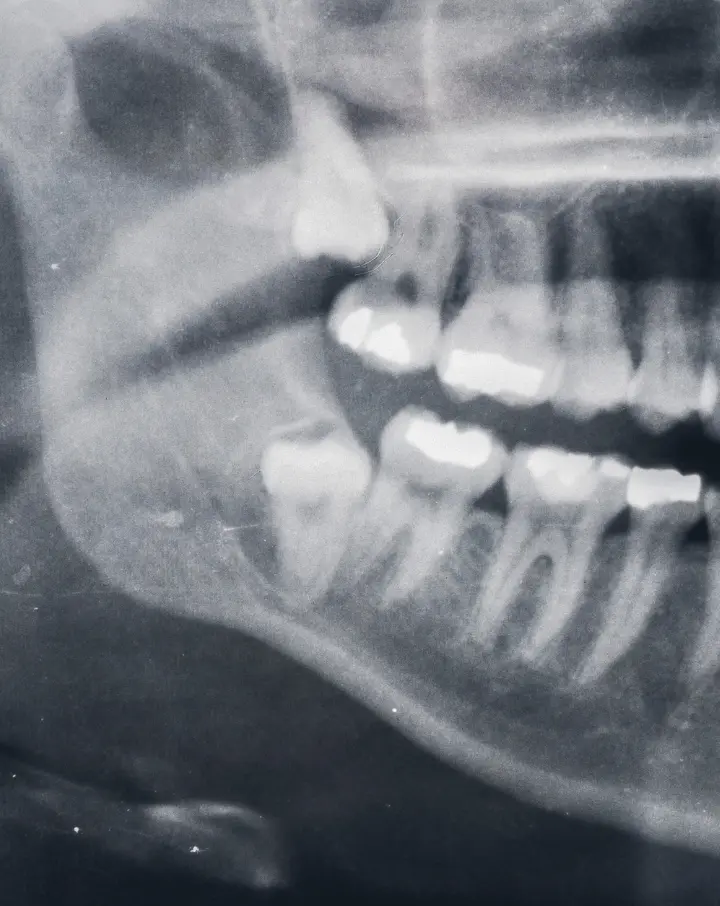

Some teeth can’t be saved. Our job is to keep you comfortable, explain your options, and choose the least invasive plan that will work. At Holly Dental Associates, our dentists perform many routine and surgical extractions in our office. We use digital X-rays and on-site 3D CBCT when needed, so we can see roots, nerves, and sinuses clearly and make an informed plan the same day.

Wisdom teeth are the last molars to come in and often there is not enough space. They can trap bacteria under the gums, push on nearby teeth, or damage the second molar. We use a panoramic X-ray or CBCT to map position and roots before recommending removal or monitoring.